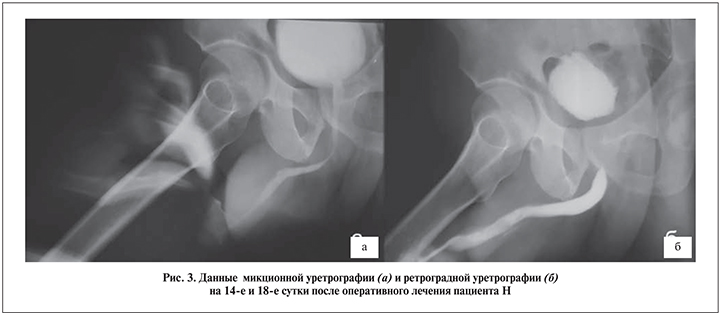

Результаты. Время пребывания пациентов после операции в стационаре составило от 2 до 4 дней. Всех пациентов выписывали из стационара с уретральным катетером. Амбулаторно в назначенный день выполнили ретроградную перикатетерную уретрографию (14–18-е сутки). В отсутствие затека контрастного вещества удаление уретрального катетера совмещали с выполнением микционной цистоуретрографии (рис. 3, а). В тот же или на следующий день пациент выполнял урофлоуметрию, на 18-е сутки – ретроградную уретрографию (рис. 3, б).